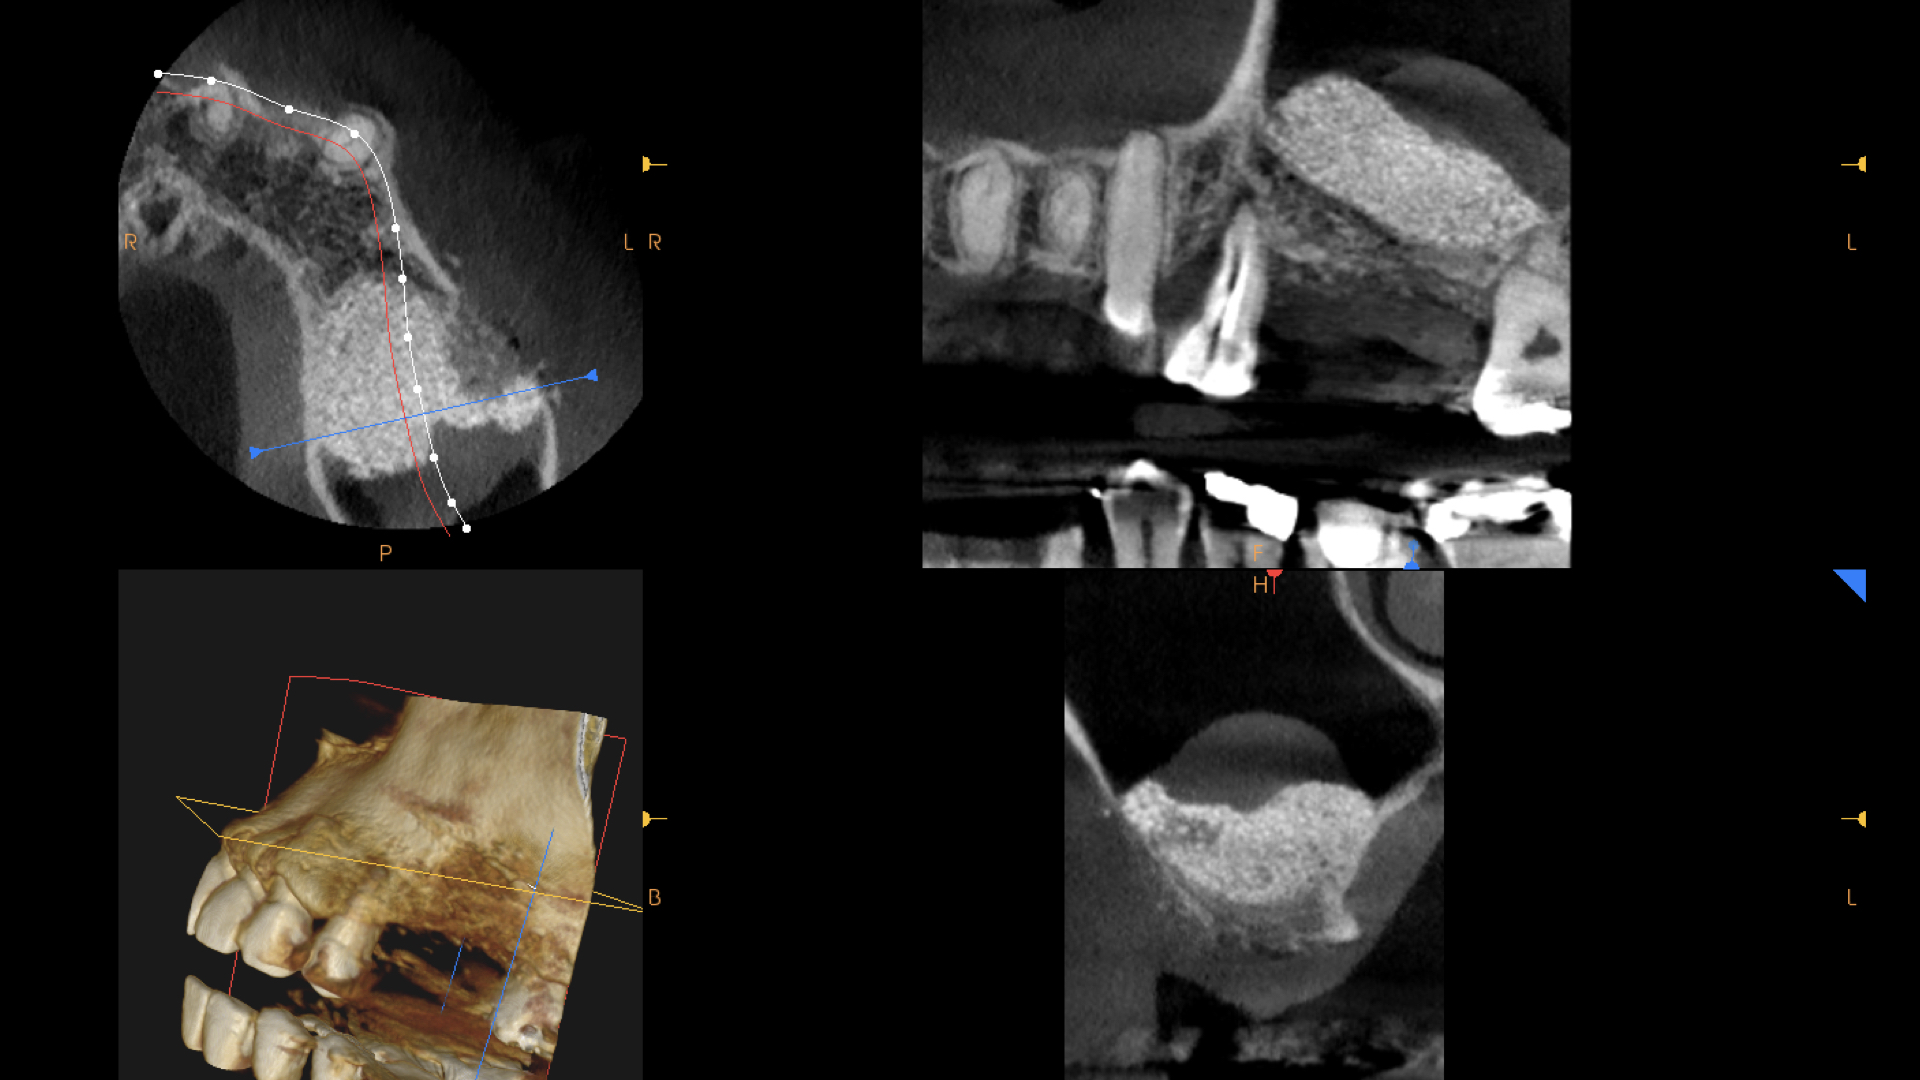

矯正が終わり、左上のインプラント治療に入ります。

もともと歯周病で骨が吸収していましたので、この部分にインプラントをおこなうには骨を造らなければなりません。

骨造成。またこの部分は上顎洞にも隣接しているので、上顎洞挙上術も必要です。

骨造成と上顎洞挙上術を同時に行いました。

骨造成したので、歯肉をかなり減張切開する必要がありました。

上の図:減張切開したため、頬側に角化歯肉が喪失しておりこのままでは歯ブラシがしにくい状態です。

下の図:口蓋側から歯肉を移植しました。(遊離歯肉移植:FGG).頬側の歯肉の形態がよくなりました。